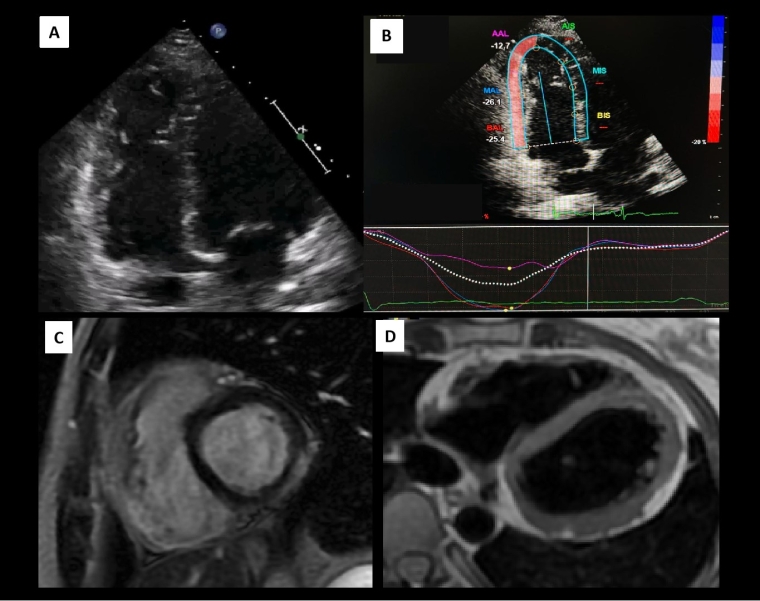

Figure 3. Representative multimodality imaging of a 25-year-old female amateur runner who was found to have an abnormal ECG during preparticipation screening and after being diagnosed with gen-positive ARVC. (A) The apical 4-chamber TTE view focused on the RV shows an isolated dilation of the RV apex (Figure 3A) and dyskinesia of this segment (Video 3.1). this suggests the presence of an RV apical aneurysm. (B) The speckle tracking analysis of the RV free wall shows preserved longitudinal strain at the basal and medium RV segments while a markedly reduced deformation at the apex. In addition, the apical segment exhibits a post-systolic shortening, confirming another pathological sign of ARVC, mechanical dispersion. The short axis SSFP cine sequences showed dilated RV with small aneurysms in the lateral segments and lateroapical hypokinesia (Video 3.2) C) Short-axis LGE sequence with basal inferolateral subepicardial enhancement. D) 4-chamber T1-weighted sequence showing fatty infiltration at the inferolateral basal and lateral midventricular segments.

ARVC: arrhythmogenic right ventricular cardiomyopathy; ECG: electrocardiogram; LGE: late gadolinium enhancement; RV: right ventricle; SSFP: steady-state free precession; TTE: transthoracic echocardiography